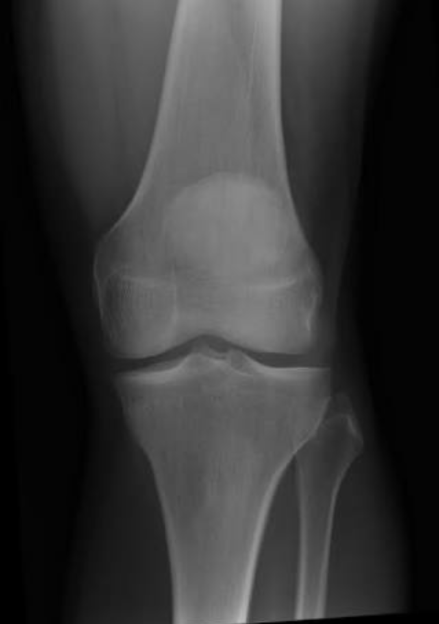

Normal x-ray knee joint

X-Ray 1: Shows the comparative pictures between normal and severe osteoarthritis

X-ray 1 shows the normal knee joint and anteroposterior (AP) view plus a lateral view of the OA affected knee joint. The radiographic hallmarks of primary osteoarthritis include nonuniform joint space loss, osteophyte formation, cyst formation and subchondral sclerosis. At first, only minimal, nonuniform joint space narrowing may be present. The involved joint spaces have an asymmetric distribution.